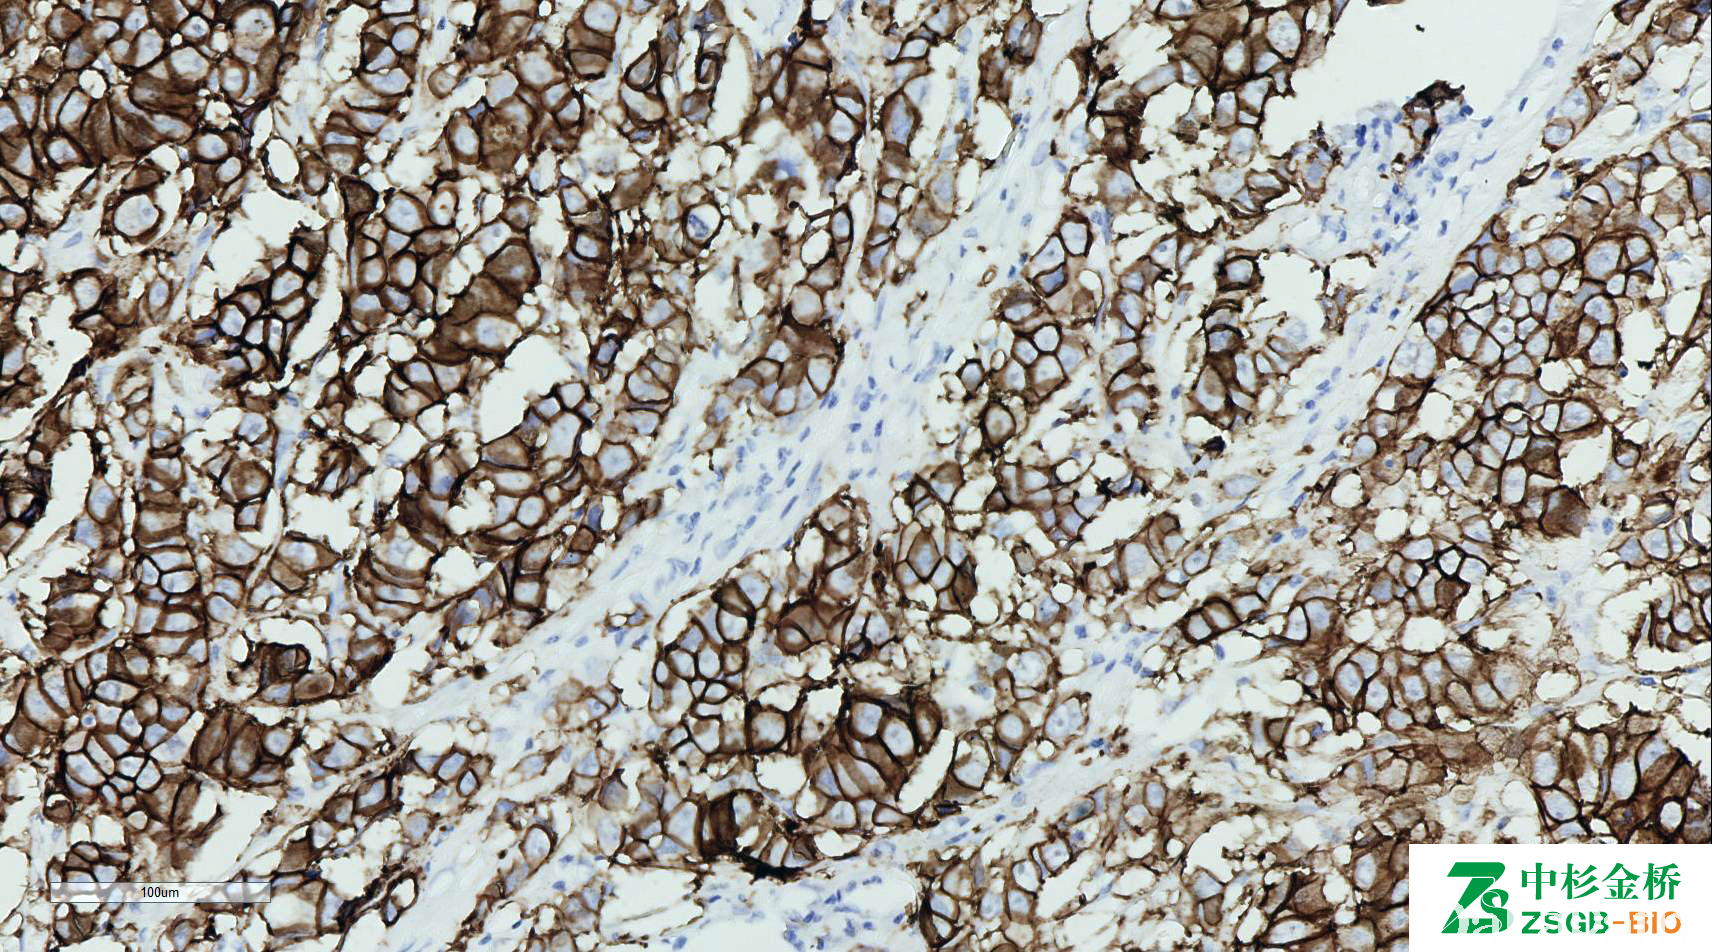

HER2

人类表皮生长因子受体 2,为 190kD 跨膜糖蛋白,具有酪氨酸酶活性。

信号定位: 胞膜

乳腺癌分型及靶向治疗病人选择,乳腺癌不良预后指标;

胃及胃食管交界处腺癌靶向治疗选择。